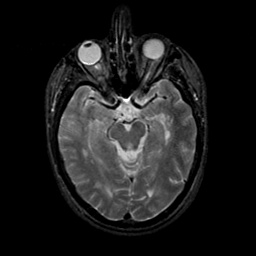

MR Study #9, April 14, 1991 -- Slice #20